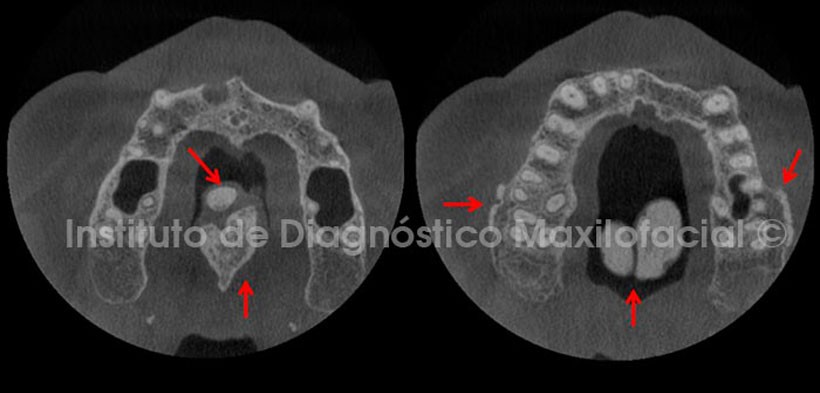

Así mismo, las vistas axiales nos muestran la distribución irregular de esta entidad. Por otro lado, también se observa la presencia de zonas de exostosis en la tabla ósea vestibular a nivel de la región de los molares (Fig. 2).